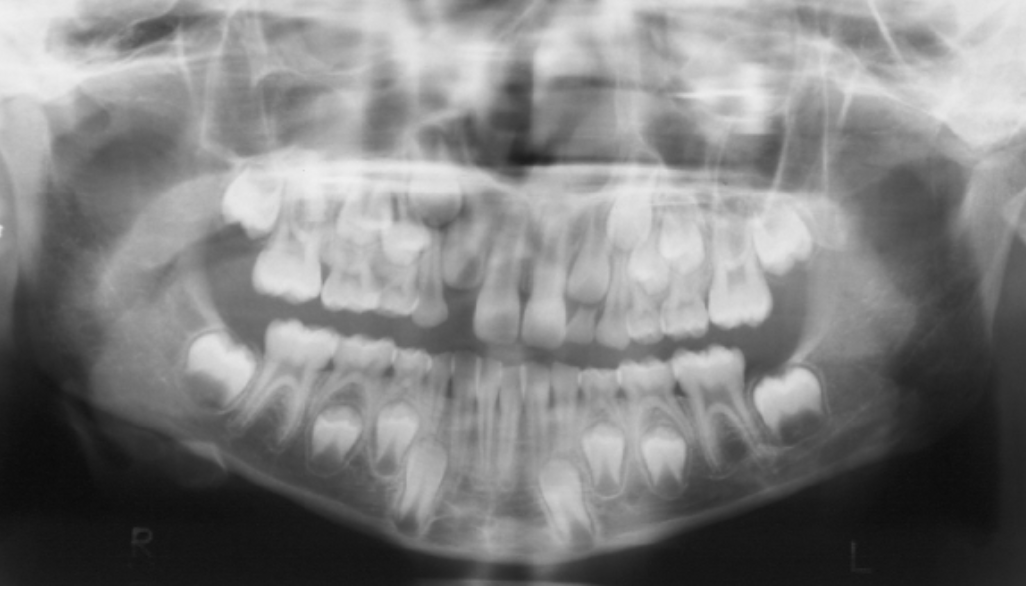

B

This patient is 7 years old. Mandibular centrals and laterals have erupted as well as maxillary centrals. Are you concerned that maxillary laterals have not yet erupted. Please see panoramic radiograph below. Which of the sentences is correct?

A) Maxillary lateral eruption is delayed given this patient's age.

B) Mandibular teeth usually erupt before the maxillary corresponding teeth, so it is not a concern maxillary laterals have not yet erupted.

C) Maxillary and mandibular corresponding teeth usually erupt at the same time, so maxillary permanent laterals may have to be brought into the arch surgically.

D) $Maxillary permanent laterals are ectopic.